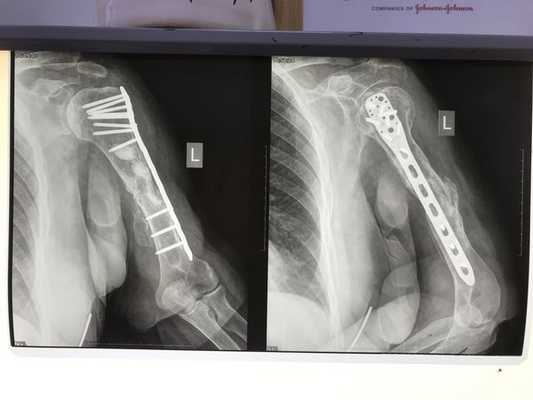

Была выполнена открытая репозиция (сопоставление фрагментов кости) и остеосинтез (фиксация) плечевой кости пластиной.

Послеоперационный период, со слов пациентки, проходил гладко. Рана зажила первично. Но через пару месяцев появился хруст и боль в области оперированного плеча. Симптомы усиливались, и постепенно появилась разболтанность в плече. Остеосинтез оказался несостоятельным — пластина не держала отломки плечевой кости.

- Сделали передний доступ к плечевой кости — по рубцу от предыдущей операции. Удалили пластину. При осмотре плечевой кости выявили серьёзное нарушение качества отломков кости и выраженное поражение мышц.

- Выполнили остеосинтез прямой пластиной LCP.

Через год выяснилось, что перелом не сросся. Пластина была нестабильной, женщина жаловалась на хруст и щелчки в области плеча.